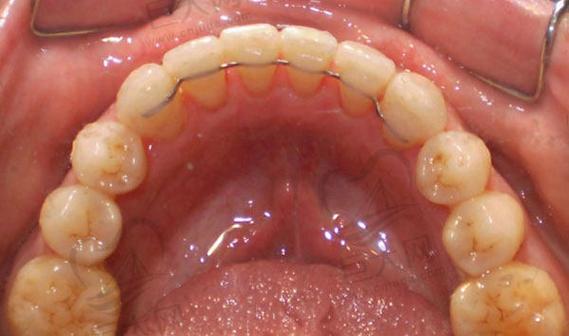

- 结构: 通常由一根细小的、光滑的金属丝(多为不锈钢或贵金属合金) 弯制成与牙齿舌侧面贴合的弧形,并通过特殊的粘接材料固定在每颗前牙的舌侧面靠近牙龈的位置(通常是牙齿的邻接点下方)。

- 位置: 完全位于牙齿内侧,从外面完全看不到。